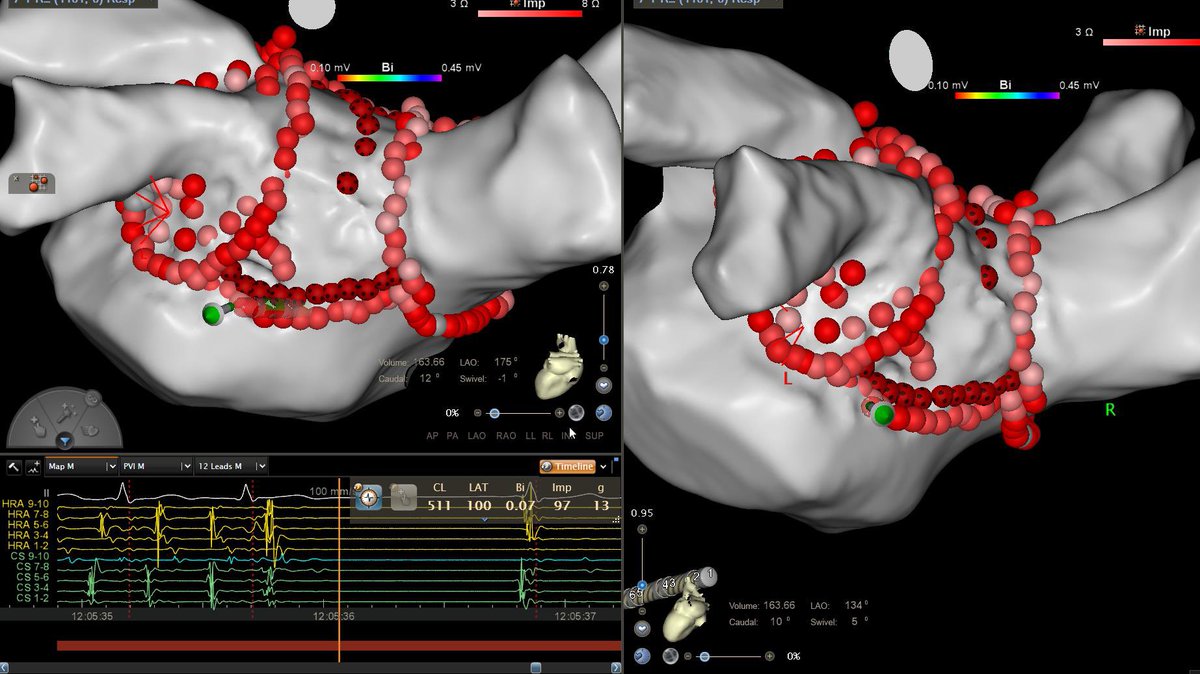

Tapped out on this Summit PVC. Earliest site GCV within 1cm of LM. Ablated from LVOT, RVOT, prox GCV. Half NS, 30W lesions for 3 min endocardial, only got temp suppression. Any other conventional options? Roderick Tung Amin Al-Ahmad, MD Anand Alex Turin AFPanico #EPeeps